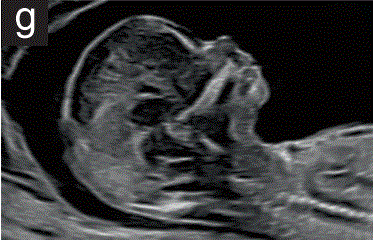

(3.6)头部/面部的中矢面也可用于评估后颅窝,并可显示颅内半透明(第四脑室)和脑干,作为开放性神经管缺陷和囊性后颅窝畸形的筛查切面(图2g)。

胎儿mt是什么检查什么疼吗【文献学习/规范指南】ISUOG实践指南(2023更新): 11-14周胎儿超声检查(全文)_https://www.jmylbn.com_新闻资讯_第12张

图2 11+0至14+0周时,可作为详细胎儿超声检查的一部分获得的解剖图。

(g) 胎儿头部正中矢状图,显示面部轮廓。在这个平面上可以评估许多结构,包括前额、鼻梁、鼻骨、上颌骨和下颌骨。后颅窝的解剖结构也可以通过丘脑、脑干、IT、脉络丛和大池的显示来检查